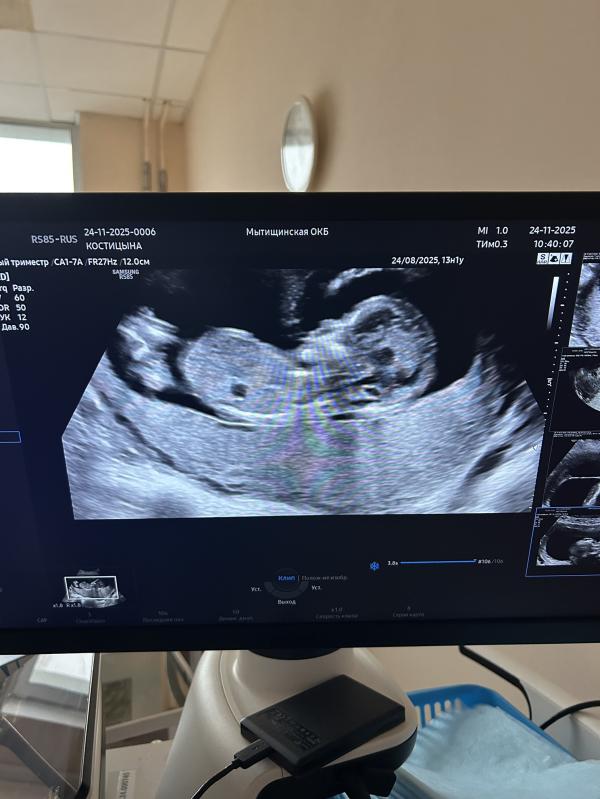

Сходила на скрининг!

Амниотический тяж никак не трогает МАЛЫШКУ, такая особенность строения плаценты.

На три дня опережает 13.4 дня по скринингу

Все в норме❤️

@kat_insta, предположили девочку. Гладенько там 😄